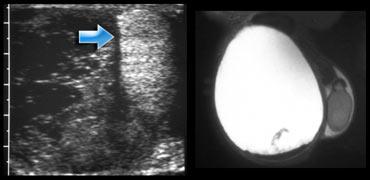

Testicular rupture

Vỡ tinh hoàn được biểu hiện trên siêu âm là những thay đổi khu trú về độ hồi âm của tinh hoàn, tương ứng với các vùng xuất huyết hoặc nhồi máu trong tinh hoàn ở bệnh nhân có tụ máu bìu.

Đường gãy rõ ràng chỉ được xác định trong dưới 20% các trường hợp, mặc dù những thay đổi có thể nhìn thấy được ở đường viền tinh hoàn là một phát hiện thường gặp.

Bên trái là một trường hợp phức tạp.

Siêu âm cho thấy một tràn máu màng tinh hoàn lớn.

Có nghi ngờ liệu cấu trúc tăng âm đó có thực sự là tinh hoàn hay không.

MRI đã được thực hiện và không tìm thấy mô tinh hoàn, vì vậy chúng ta phải kết luận rằng cấu trúc tăng âm này là kết quả của một khối máu tụ mới.

Bên trái là một bệnh nhân khác bị vỡ tinh hoàn, được phát hiện trên CT bụng.

Trên siêu âm có một vùng không đồng nhất lớn không xác định được tinh hoàn do vỡ.